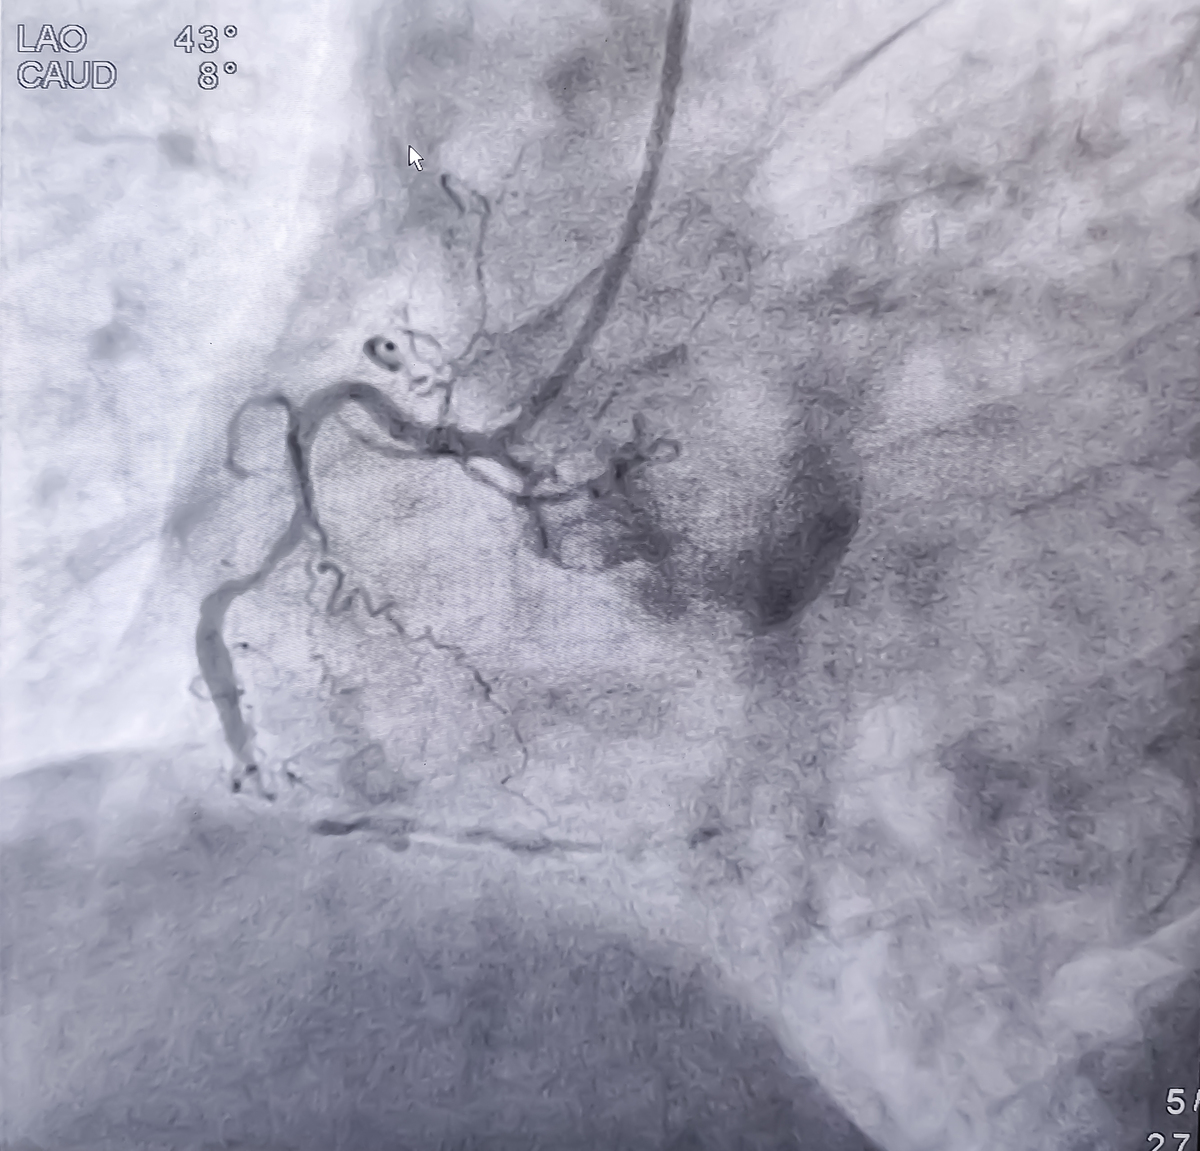

超声造影检查诊断结果显示,右侧颈动脉存在易损斑块破裂,并形成了溃疡。此外,还发现合并自由漂浮血栓形成,右侧颈内动脉起始部存在中度狭窄。